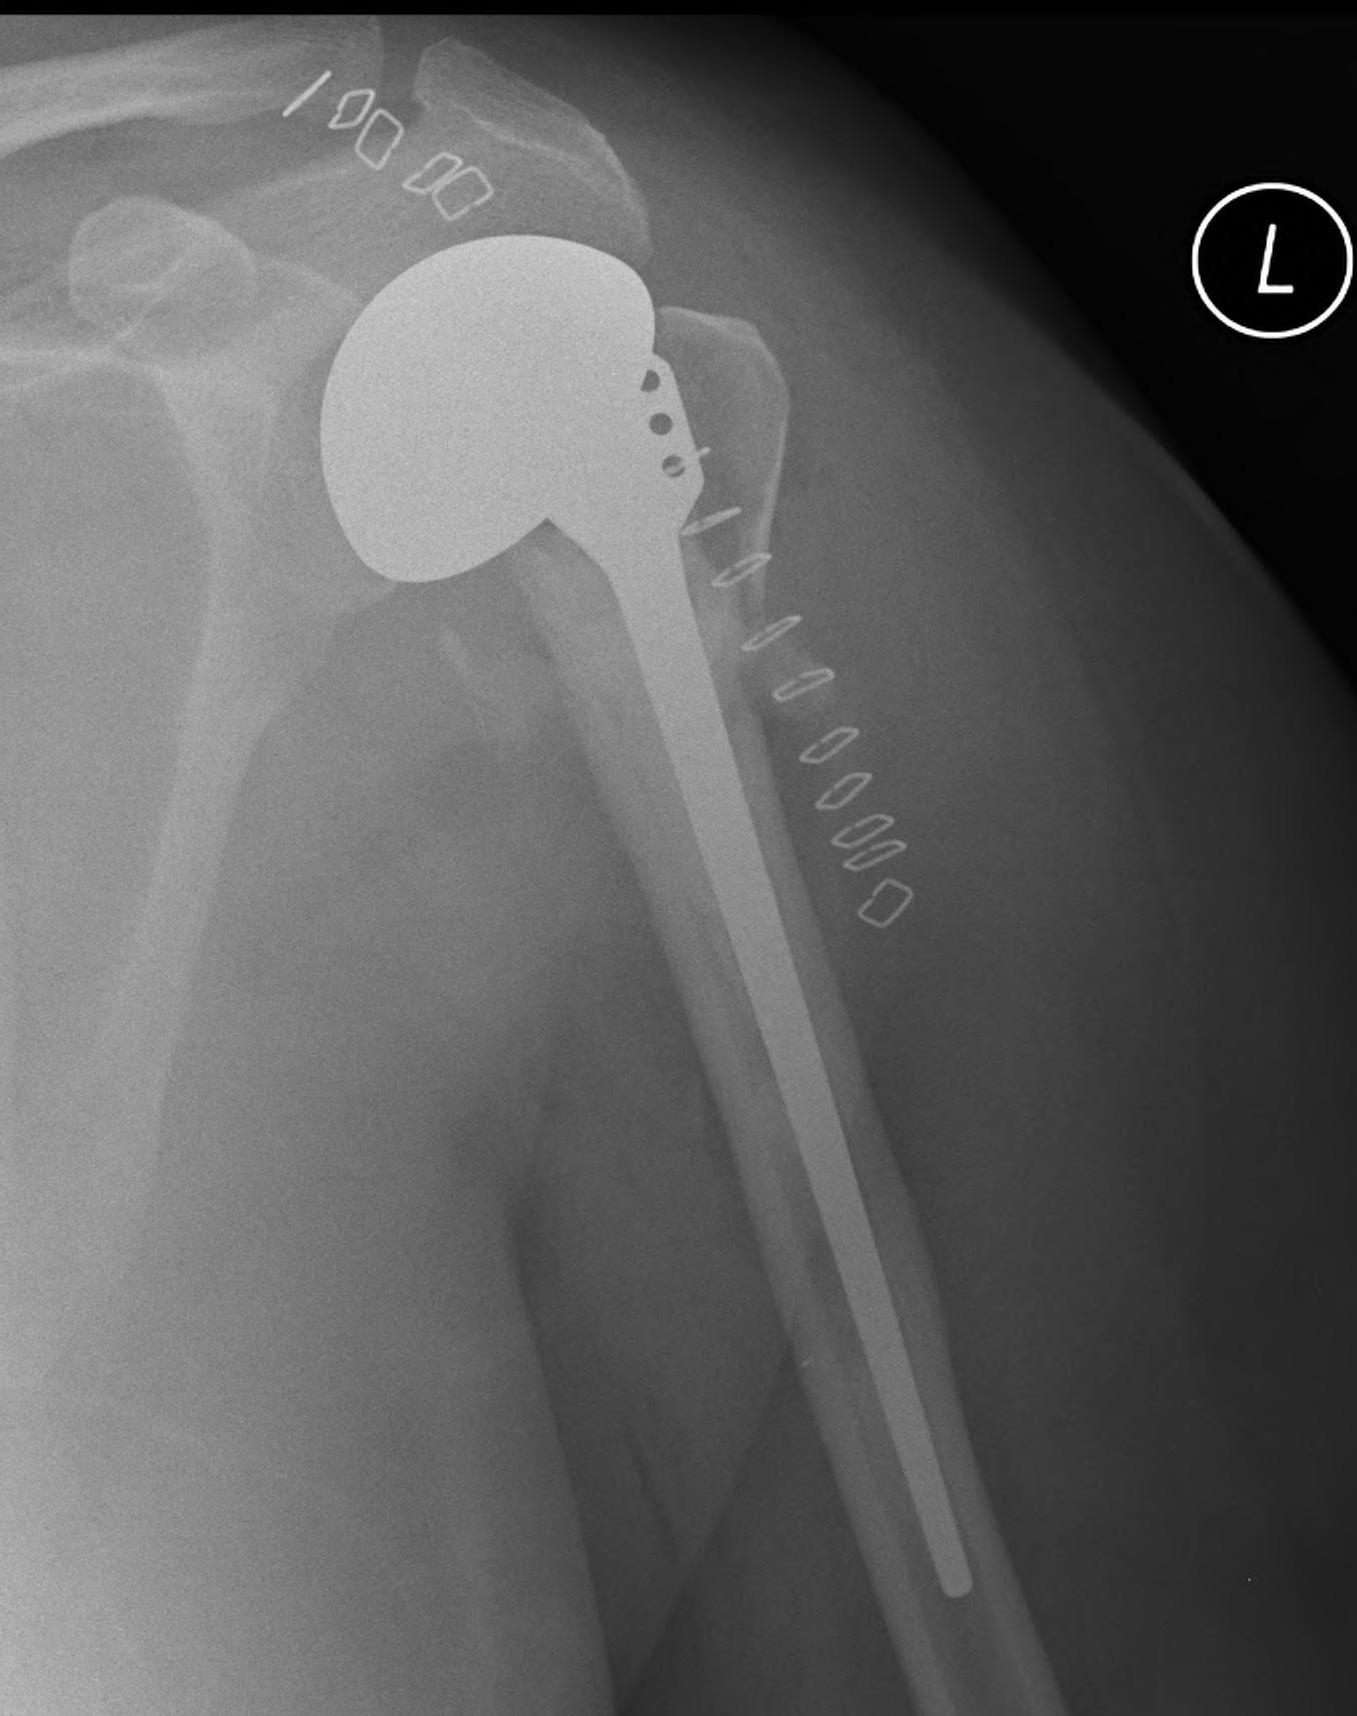

proximal humerus fracture Background ORIF with locking plate Arthroplasty Greater tuberosity fractures Lesser tuberosity fractures / avulsions Book traversal links for Proximal humerus fractures ‹ Pectoralis Major Tears Up Background ›